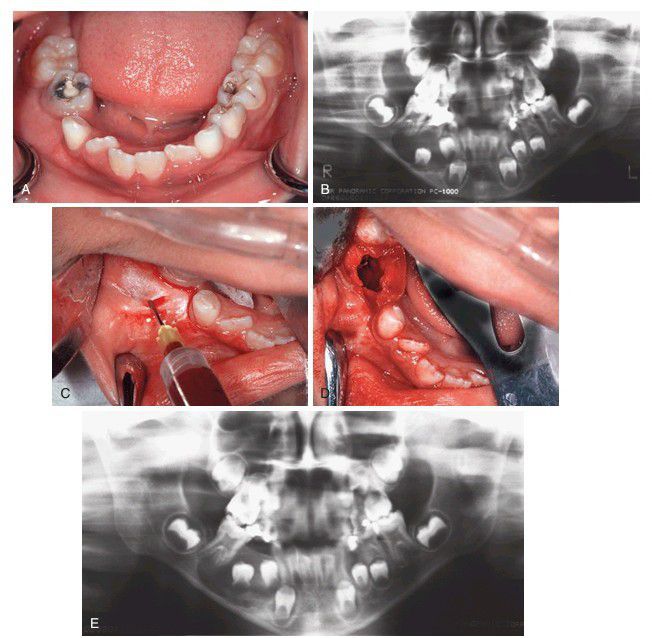

Marsupialization of a cyst in the right mandible associated with unerupted teeth. (A) Swelling around the right second deciduous molar. (B) Radiographic appearance before marsupialization. Note the large radiolucent lesion and displacement of the second right premolar toward the inferior border (compare with the opposite side). Cystectomy would probably injure or necessitate the removal of the premolars, so it was marsupialization of the cyst that was performed instead. (C) Aspiration to determine whether the lesion was fluid filled (cystic). (D) The lower right deciduous second molar was removed, and the cyst was opened through the socket (decompressed). (E) Panoramic radiograph taken 5 months after surgery showing bone fill and eruption of the premolars.